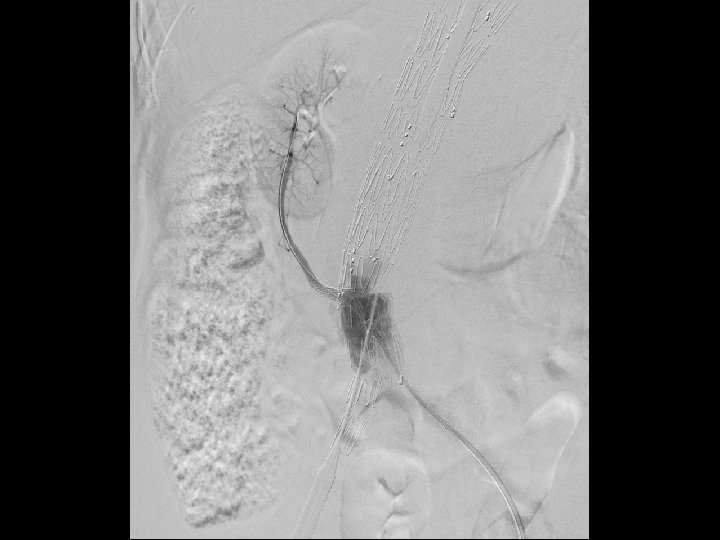

Technique • Initially the left subclavian was bypassed and plugged. • Two Cook TX 2 TAA endografts were placed, the first covering the occluded left SCA. • Segment three was a Cook Zenith endograft with branches for the celiac, SMA, and left renal artery. • Segment four was a customized fenestrated bifurcated endograft. • The IMA was chronically occluded. • Atrium stent for the fenestrated component and self expandable stents for branched segments. • Procedure was staged to prevent spinal cord ischemia, the SMA branch was sealed 2 weeks after initial endovascular procedure.